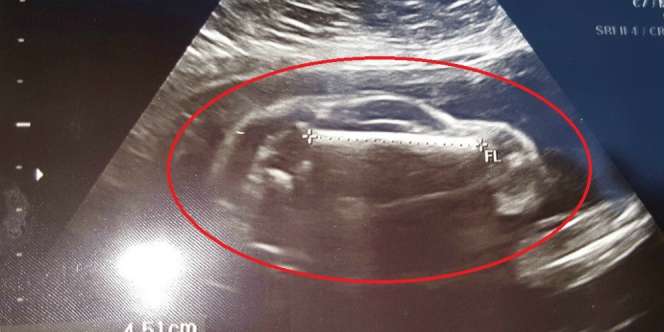

Penampakan Janin Dalam Kandungan (Reddit)

Namun, tidak dengan hasil USG istri pengguna Reddit dengan akun Brewhaus3223 ini. Bentuk janin yang tampak dari hasil USG itu sungguh mengejutkan. Sepintas tak terlihat seperti bayi, tapi lebih menyerupai mobil sport.

Melalui media sosial Reddit itu, dia menulis telah memeriksakan kandungan istrinya yang berusia 24 minggu. Seperti calon orangtua lainnya, mereka juga berdebar ingin melihat bentuk janin dalam kandungan.

Namun, betapa terkejutnya mereka saat melihat bentuk janin dalam kandungan itu mirip mobil balap. “ Istriku hamil mobil sport,” tulis Brewhaus3223, dikutip Dream dari laman Metro.co.uk, Selasa 14 Juni 2016.